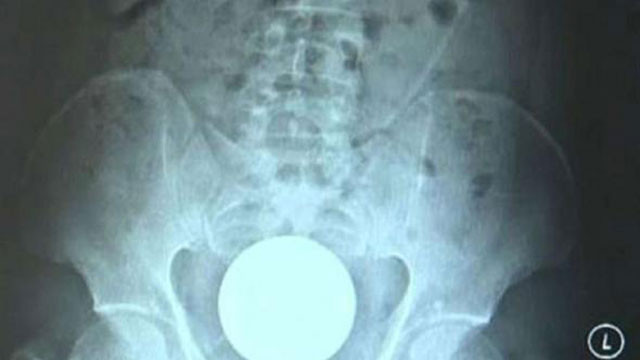

Çin’de yaşanan tıbbi bir olay ülke gündemine oturdu. Çin’in Guangdong bölgesindeki Dongguan’da yaşayan 31 yaşındaki Xiao Ming, hastaneye karın ve mide ağrısı şikayetiyle giderken, yapılan incelemeler sonucunda vücudunda bir cisim bulundu. Röntgen sonuçlarına bakan doktorlar neye uğradıklarını anlayamadan, Ming utana sıkıla yaşadığı sorunun sebebini söyledi.

Ming, sadece eğlence olsun diye anüsüne camdan bir top soktuğunu ve bunu daha sonra içinden çıkaramadığını söyledi. Yaklaşık 7 saat boyunca 7 santimetre çapındaki topu çıkarmaya uğraştığını söyleyen Ming, bu açıklamanın ardından hızla ameliyata alındı.

Acı çeken adamın operasyonu da zorlukla tamamlandı. Rektumunda sıkışan cam topu almakta zorlanan doktorlar daha sonra özel bir kerpetenle topu vücuttan çıkarabildi.

Ameliyatı yürüten Dr. Ye, “Hastanın iç organlarına zarar vermemek için incelikle çalıştık. Midesine bastırarak topu çıkmaya hazır hale getirdik ve daha sonra kerpetenle aldık” dedi. Dr. Ye, müdahalenin tam zamanında yapıldığını dile getirirken, “Eğer geç kalsaydık hasta septik şok yaşayabilir ve iç organlarına kalıcı zararlar verebilirdi” dedi.